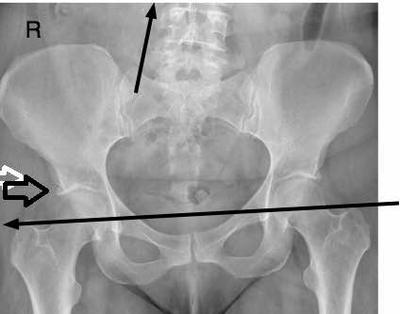

FAIS and a short leg

Pain has been going on for over 5 months. X-ray of hips indicated MILD osteoarthritis, slightly worse on left side. If it is mild, why is the pain so severe?

Find out if you have a short leg, and wear an inexpensive insert in your shoe.

Talk to your children about getting leg length checked now, and doing daily exercises. This is hereditary, especially if they have a condition called FAIS; you'll find out more about it at Chiropractic Help by using the Site Search function. You'll find some hip exercises the same way.